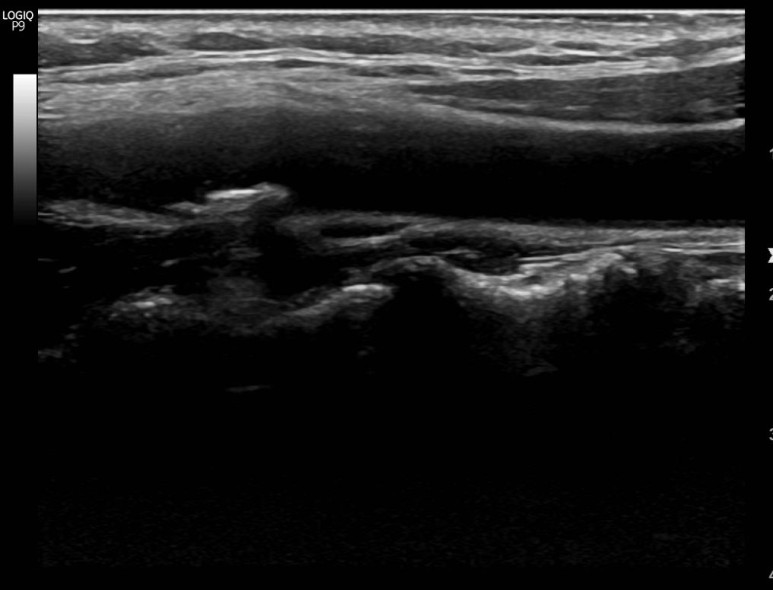

경동맥 초음파로 확인되는 동맥 경화반

뇌졸중의 원인이 될 수 있기 때문에 엄격한 고지혈증 관리가 필요합니다.